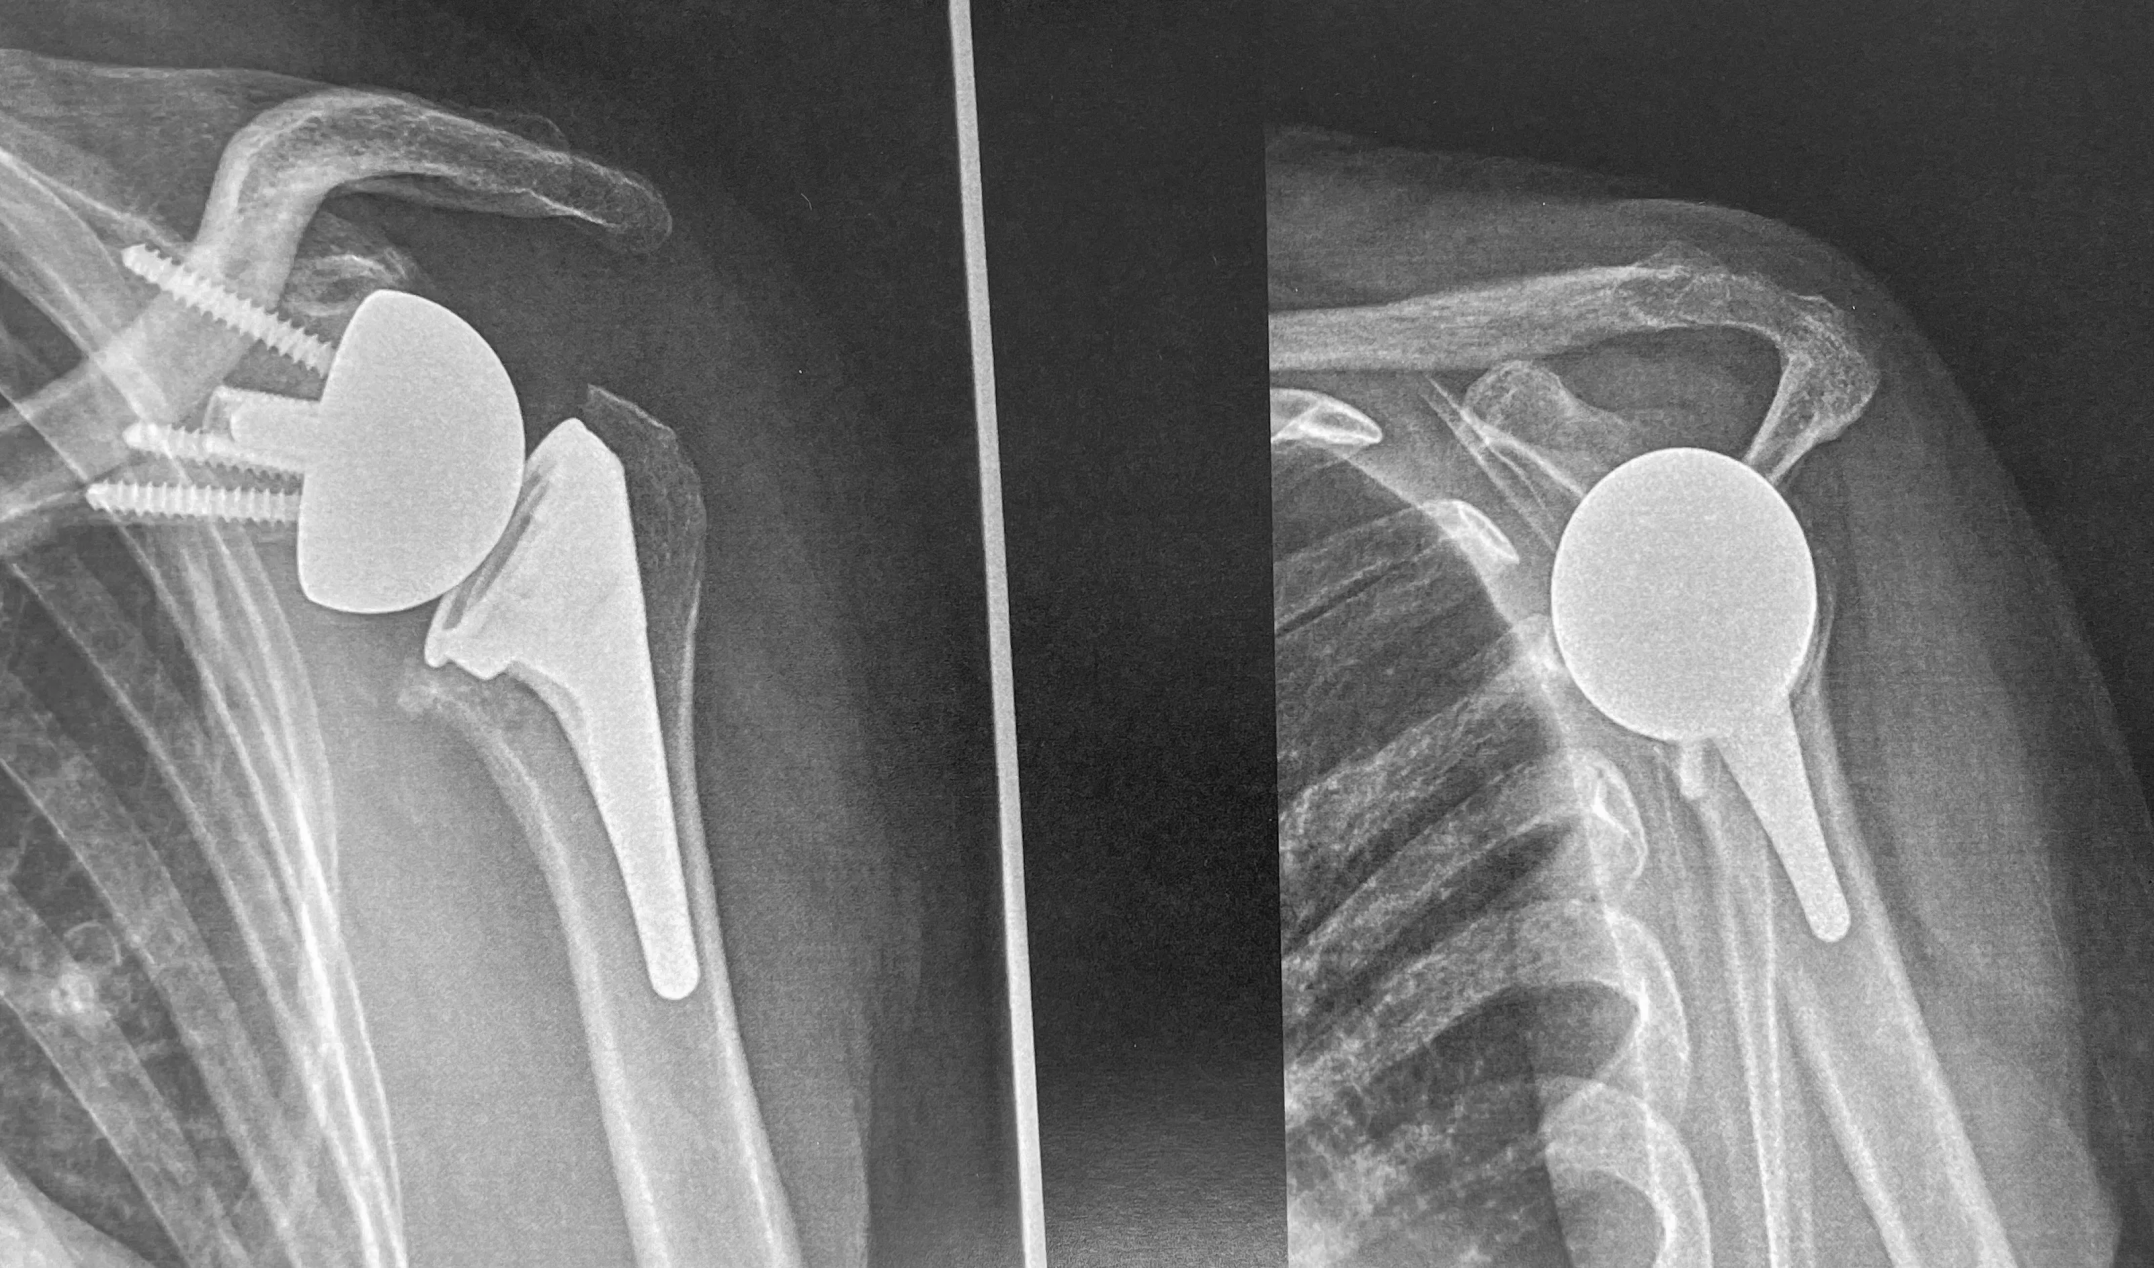

LES PROTHÈSES ANATOMIQUES DE L'ÉPAULE

Les prothèses anatomiques sont des implants qui vont remplacer l'anatomie native des surfaces articulaires de la tête humérale et de la cavité glénoïdale.

L'implant huméral est composé d'une tige prothétique qui va etre insérée dans l'humérus et d'une "calotte" qui vient remplacer la tête humérale. Ces implants sont en titane ou en alliage chrome-cobalt.

L'implant glénoïdien est en polyéthylène. Il s'agit d'une matière plastique très resistante.

Pour que l'on puisse proposer une prothèse anatomique, il faut impérativement que les tendons de la coiffe des rotateurs soient sains et fonctionnels.

Il existe plusieurs types de prothèses anatomiques : des prothèses de resurfaçage sans tige humérale, des prothèses à tiges courtes qui ont pour but de préserver le capital osseux et des prothèses à tiges longes qui peuvent être utilisées lors de changements prothétiques.

LES PROTHÈSES INVERSÉES DE L'ÉPAULE

Ce sont des prothèses qui sont utilisées lorsque les tendons de la coiffe des rotateurs sont rompus ou non fonctionnels.

Elles sont composées d'une tige humérale qui présente une cupule à sa partie supérieure et une pièce glénoïdienne qui a la forme d'une hémisphère. Le muscle deltoïde seul permettra l’élévation du bras.

Leur conception est dite "inversée" car la partie shérique est positionnée sur le versant glénoïdien contrairement à une épaule originelle. Cette architecture spécifique leur permet de pouvoir restaurer la fonction de l'épaule grâce à l'action du deltoïde qui devient le moteur principal de l'épaule.